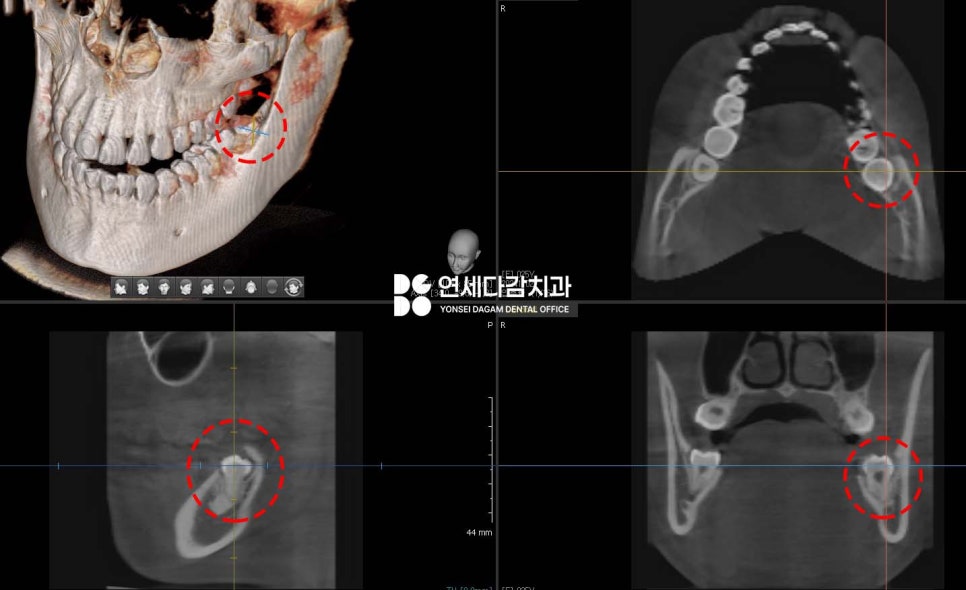

먼저 CT를 촬영하여 주변 구조물을

정밀하게 분석한 뒤 발치 계획을 세웠습니다.

구강 검사 결과,

아래 매복 사랑니 주변으로

특히 심한 부종이 관찰되었으며,

해당 부위를 촉진했을 때

고름이 나오기도 했습니다.

이는 감염(지치주위염)이 진행 중임을

나타내는 명백한 징후였습니다.